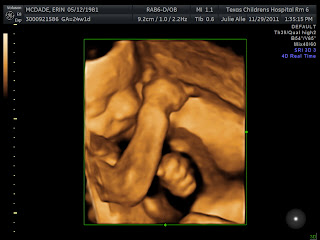

Given my medical history and clotting disorder my pregnancy is considered high risk, so we had our first appointment with a Maternal Fetal Medicine specialist today. Part of the visit was another ultrasound with some 3D images!! Do you think he looks more like a Myers or a McDade??

Our little man continues to measure bigger than average, as high as the 87th percentile for certain measurements and is estimated to weigh in at 1 lb 14 oz. In fact, he's measuring as if he's a week ahead of schedule.... but the doctors are still sticking with the March 19th due date. He's been very active lately and put on quite a dance routine during the ultrasound today (Jim claims that he's inherited that from him)! We also learned that since he's head down right now the pokes and prods to my lower abdomen and bladder, which I thought were kicks, are probably more likely to be karate chops. :)